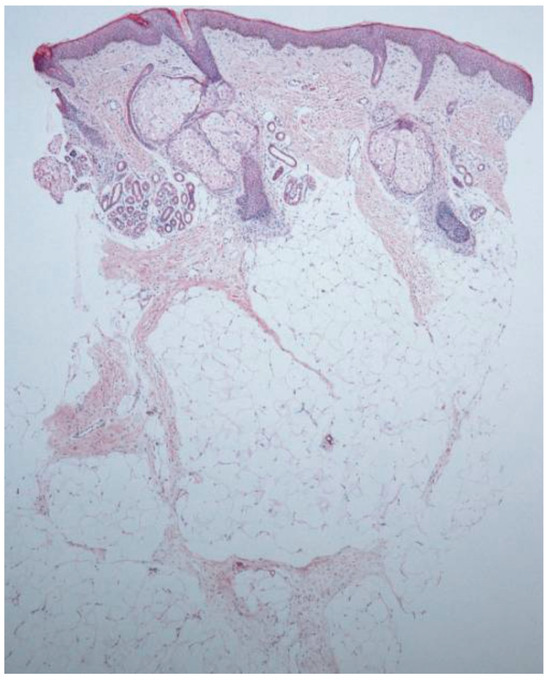

3.1.1. Nevus Psiloliparus

| Alopecic scalp lesion | Absent hair follicles, lobular fat infiltration of the dermis, and isolated arrector pilli muscles [8] Fibrovascular stroma [9] Degenerated muscle fibers of arrector pilli muscles [9] Potential for complex hamartomous structures such as fibrolipomas or angiolipomas [10] Retification of the epidermis and hair follicles surrounded by fibrosis and absent elastin fiber network [6] Lack of adnexal structures [11] Irregularly shaped collagen fibers in the dermis [16] Inflammatory infiltrate including mast cells [16] Diffuse adipocytes separated by congested capillaries [13] |